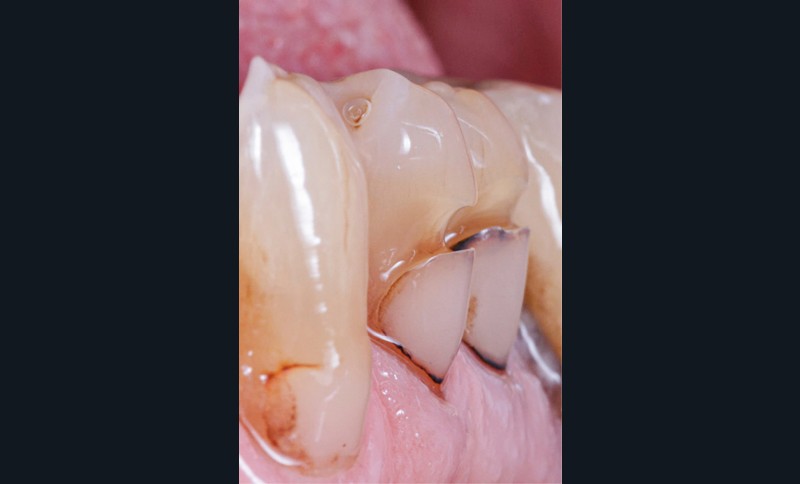

Le cas clinique illustré à partir de la fig. 10 rapporte encore une indication de bridge cantilever, mais cette fois avec un contexte occlusal de bruxomanie identifiable par des facettes d’abrasion et des écaillages de l’émail (fig. 10a et b). Un bridge présentant une armature en zircone (3Y-TZP) recouvert d’une céramique cosmétique a été choisi comme proposition thérapeutique (Laboratoire Esthetic Oral, Cogolin).

L’assemblage de ce bridge présentant une armature en zircone a été réalisé avec une colle avec potentiel adhésif (Panavia F2.0® (Kuraray)) et avec le concours d’un sablage à l’alumine sur l’intrados de l’ailette du bridge. Comme le montre la fig. 11b, l’intrados a été crayonné afin de visualiser les effets du sablage et ainsi s’assurer de sa bonne réalisation. L’apprêt a ensuite été posé sur toute la surface de l’intrados prothétique.